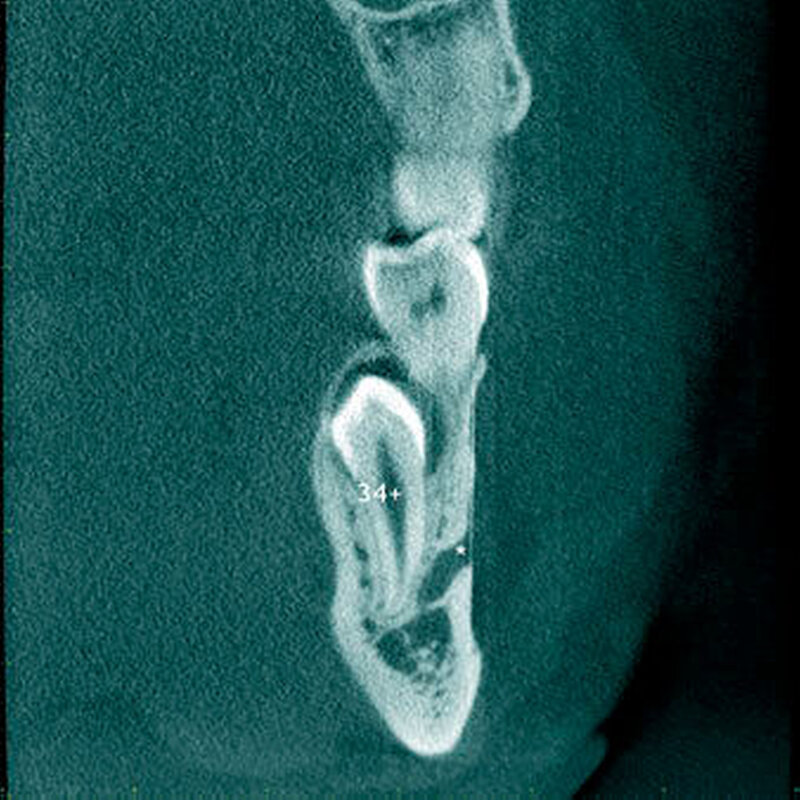

In einer aktuellen Arbeit berichteten Mossaz und Mitarbeiter (2014) über eine relativ hohe Prävalenz (22,8 Prozent) der Wurzel- resorptionen an benachbarten Zähnen, wobei besonders häufig überzählige Prämolaren zu Resorptionen führen (Abbildung 18). Für die Beurteilung der Wurzelresorptionen wurden digitale Volumentomografie (DVT) der Patienten herangezogen. In einer Studie aus China, welche ebenfalls DVT-Bilder beurteilte, wurde über eine deutlich geringere Häufigkeit von Wurzelresorptionen (1,6 Prozent) berichtet [Liu et al., 2007]. Im Gegensatz zu den Daten aus der Schweiz war Diagnose und Bewertung von Wurzelresorptionen kein primäres Ziel dieser Studie und es wurde auch keine Information über das Ausmaß der Resorptionen gegeben.

Daher könnte diese Studie leichte oder mäßige Wurzelresorptionen nicht eingeschlossen haben, was zumindest einen Teil des doch deutlichen Unterschieds in den Prozentsätzen erklären würde. Studien, welche Panoramaschichtaufnahmen zur Diagnose von Wurzelresorptionen heranziehen, berichten über Resorptionsraten zwischen 4,7 Prozent [Gündüz et al., 2008] und 7,6 Prozent [Hyun et al., 2009]. Tyrologou und Mitarbeiter (2005) berichteten sogar, dass keine Resorption im untersuchten Patientengut vorhanden waren. Allerdings wurden in dieser Studien nur Mesiodentes beurteilt, wo Wurzelresorption benachbarter Zähne eher selten vorkommen [Mossaz et al., 2014]. Generell lässt sich festhalten, dass zweidimensionale Röntgenaufnahmen für die Diagnose von Wurzelresorptionen eher ungenau sind und diese so in bis zu 50 Prozent der Fälle übersehen werden [Ericson Kurol, 1987, Heimisdottir et al., 2005; Botticelli et al., 2011; Alqerban et al., 2011a].

Bei überzähligen Zähnen werden vier morphologische Typen unterschieden: konisch (Abbildung 9), tuberkulär (höckerförmig; Abbildung 10), überzählige Zähne mit identischer Zahnform (Abbildung 11) und Odontom (Abbildung 12) [GARVEY et al. 1999]. Der konische überzählige Zahn ist ein kleiner, zapfenförmiger Zahn und zudem der häufigste Fall im bleibenden Gebiss [Rajab Hamdan 2002, Liu et al. 2007, Gündüz et al., 2008; Ferrés-Padró et al., 2009; Hyun et al., 2009; Schmuckli et al., 2010; Mossaz et al., 2014]. Er kommt oft zwischen den oberen zentralen Schneidezähnen vor und entwickelt sich gleichzeitig zur Wurzelbildung der bleibenden Schneidezähne. Konische überzählige Zähne führen meist nicht zu einer Durchbruchstörung oder -behinderung der zentralen Schneidezähne. Tuberkuläre, überzählige Zähne sind größer als der konische Typ und besitzen einen zusätzlichen charakteristischen Höcker oder Tuberkel der Zahnkrone. Sie kommen oft gepaart vor und liegen in der Regel palatinal der oberen mittleren Schneidezähne. Im Gegensatz zu konischen überzähligen Zähnen brechen die meisten tuberkulären nicht in die Mundhöhle durch und es kommt nicht selten zur Durchbruchstörung oder -behinderung der zentralen Schneidezähne [Mason et al., 2000; Minguez-Martinez et al., 2012]. Überzählige Zähne mit identischer Zahnform sind Zähne, welche vom eigentlichen Zahn in der Lage (also in der Zahnreihe gelegen) und Form nicht zu unterscheiden sind.

Dagegen haben überzählige Prämolaren in der Regel eine geneigte oder normale Eruptionslage [Mossaz et al., 2014]. Überzählige Zähne können normal durchbrechen oder bleiben retiniert beziehungsweise teilretiniert. Frühere Studien berichteten, dass zwischen 15 Prozent [Tay et al., 1984) und 34 Prozent [LIU et al., 1995] der überzähligen Zähne erst im bleibenden Gebiss durchbrechen. Im Gegensatz dazu eruptieren 73 Prozent der überzähligen Zähne bereits im Milchgebiss [Humerfelt et al., 1985}. Nicht-durchgebrochene überzählige Zähne können asymptomatisch bleiben und werden erst zufällig während einer routinemäßigen Zahnkontrolle auf einem Röntgenbild – in der Regel einer intraoralen Aufnahme – diagnostiziert. Überzählige Zähne werden jedoch auch dann entdeckt, wenn ein bleibender Zahn in seinem Durchbruch entweder verzögert oder in seiner Lage verschoben ist.